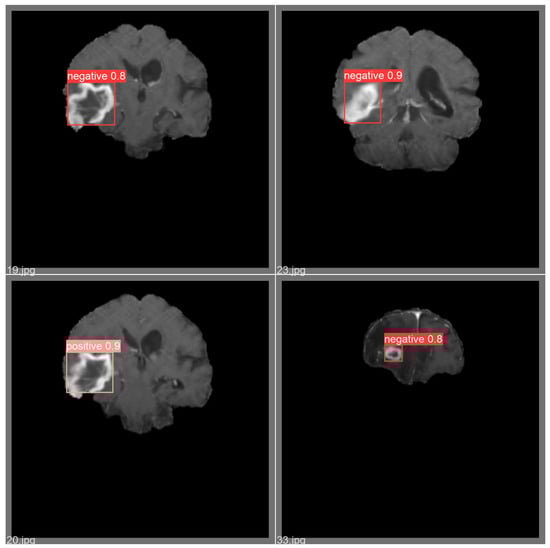

4. Experimental Results and Discussion

4.1. Overall Model Performance